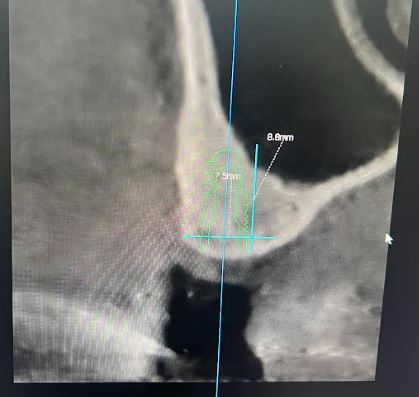

I have this implant case for tooth #28. I am worried about the anterior loop of the IAN here. It looks like it terminates at slice 62 and 63 but then I have a circular radiolucent area in slice 65. Do you think this is still the mental? If so I have about 10mm from the crest of the ridge. Do you think I’d be safe with an 8 mm implant here?

Just looking at what you provided it looks like there is sufficient room for an 8mm implant and that other slice I believe around 65 just looks like a void around the bone that looks similar to the pano version of the cbct and doesn’t present in other slices, nerve appears to be below that area.